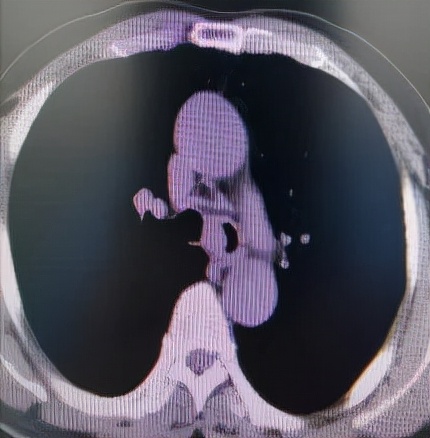

经过充分细致的各项准备工作,手术如期进行。麻醉科刘淑杰副主任医师给患者经喉罩套气管插管(8mm),在充分气道保护下插入电子支气管镜观察病变,隆突区可见菜花状新生物,表面凹凸不平,血供较丰富,新生物累及左主支气管导致管腔狭窄约80%,新生物也累及右主支气管导致管腔狭窄约60%,手术难度比预计还要高。因病变刚好位于隆突区,操作稍有不慎,很容易将隆突穿漏。术中于世寰主任熟练地交替应用各种设备,于新生物处反复施以激光蚀刻、电切刀电切、圈套器套取、二氧化碳冷冻冻取等操作,削瘤过程中的出血,应用APC充分予以止血,完美的完成了削瘤手术。术后患者很快苏醒,醒后患者的第一反馈就是呼吸顺畅多了。

削 瘤 后